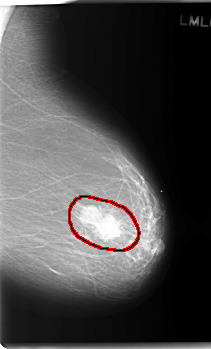

C_0176_1.LEFT_MLO

LEFT_MLO LINES 5928 PIXELS_PER_LINE 3584 BITS_PER_PIXEL 12 RESOLUTION 50 OVERLAY

FILE: C_0176_1.LEFT_MLO.OVERLAY

TOTAL_ABNORMALITIES 1

ABNORMALITY 1

LESION_TYPE MASS SHAPE LOBULATED MARGINS MICROLOBULATED

ASSESSMENT 5

SUBTLETY 5

PATHOLOGY MALIGNANT

TOTAL_OUTLINES 1

BOUNDARY